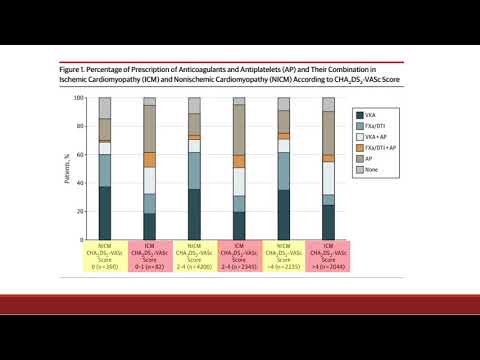

Resultados en pacientes con fibrilación auricular en cardiopatía isquémica vs no isquémica: Registro GARFIELD-AF